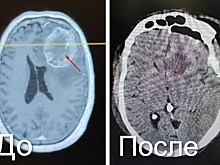

Сильная боль и тошнота оказались симптомами крупной опухоли мозга у кузбассовца

Новости медицины

18 ноября